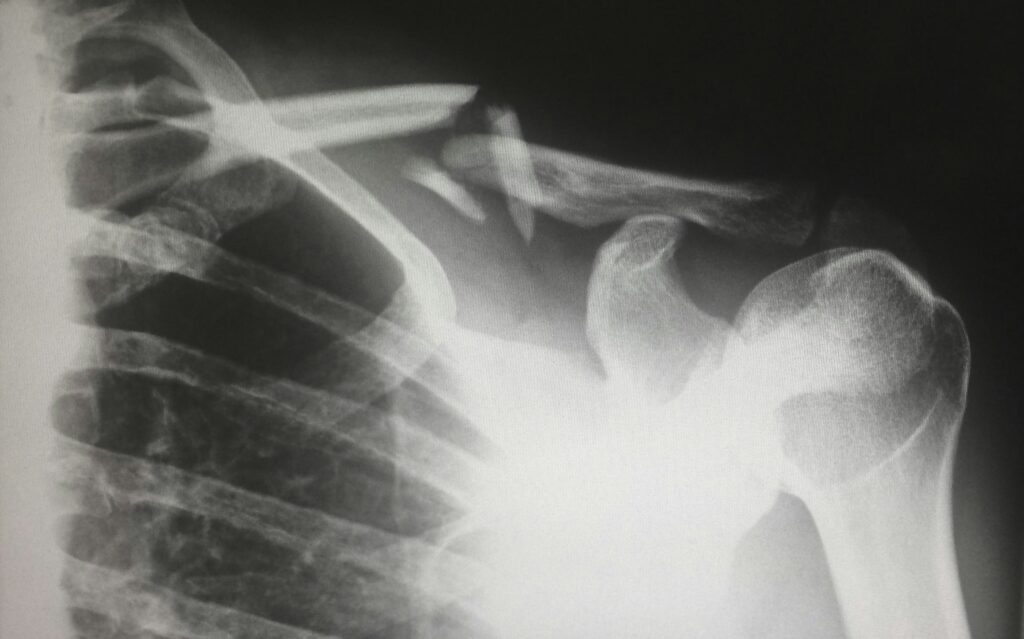

التشخيص

يبدأ التشخيص دائمًا بـ الفحص السريري حيث يقوم الطبيب بتقييم الحركة ونقاط الألم.

ثم قد يطلب:

- الأشعة السينية لتوضيح حالة العظام والمفصل.

- التصوير بالرنين المغناطيسي لتشخيص التمزقات أو مشاكل الأوتار.